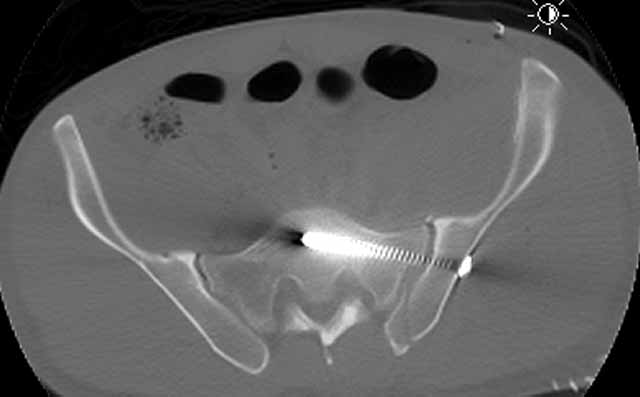

For a variety of reasons we stopped at that, placed him in traction, and repeated his films and CT.

Two days later we returned to the OR and tried a closed manipulative reduction of the SI joint-iliac fracture but it failed, so we used the lateral (iliac) window of an ilioinguinal exposure to clean, reduce, and clamp the SI joint. We stabilized it with an iliosacral screw and closed.

Under the same anesthesia, we used a prone K-L exposure to reduce the impaction fragment, fold down the posterior wall, and hold it with a plate.

Here are the films....the staple lines mark his incisions.

AP Pelvis

CT Acet

CT SI Joint

We'll use ectopic bone prophylaxis and protect his weight bearing.